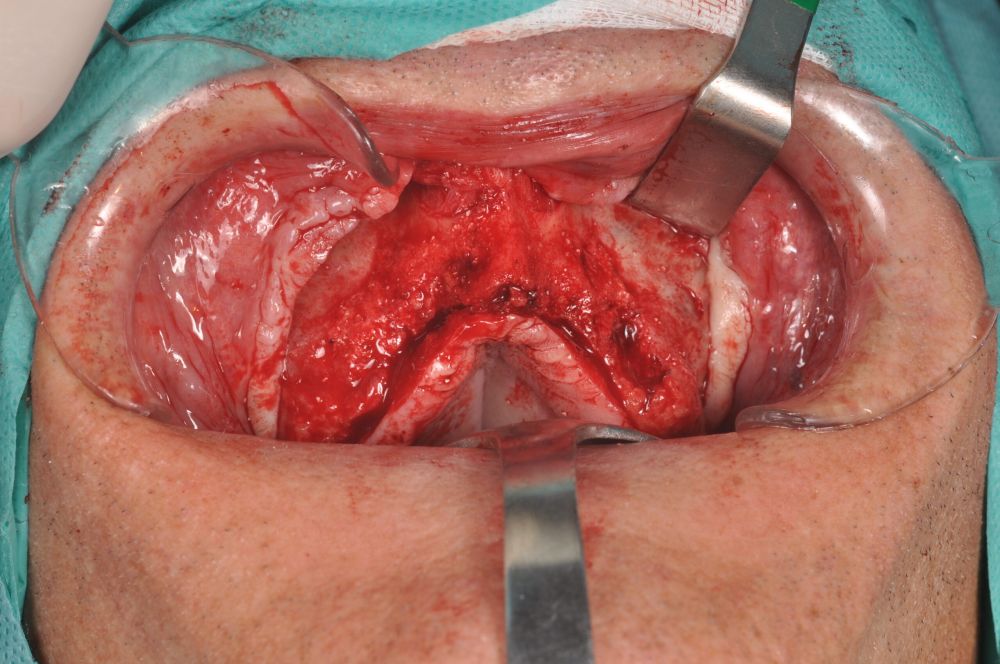

The surgical procedure was performed under general anaesthesia and nasotracheal intubation. A supracrestal incision and detachment of a maxillary flap of total thickness was made (Figures 9 and 10). The boundaries of the dissection were both infraorbital ridges, both laterally malar bodies and the anterior half of the hard palate caudally. In addition, a customized cutting guide was used so that the SI was completely in direct contact with the bone (Figure 11) and the mesh was fixed with the different 1.5 mm osteosynthesis screws in the nasal and zygomatic buttresses (KLS Martin, Freiburg, Germany) (Figure 12). The closure was performed with nonresorbable suture. Finally, the PMMA provisional rehabilitation was screwed for the immediate load, with a torque of 20 N on the implants (Figures 13-15).